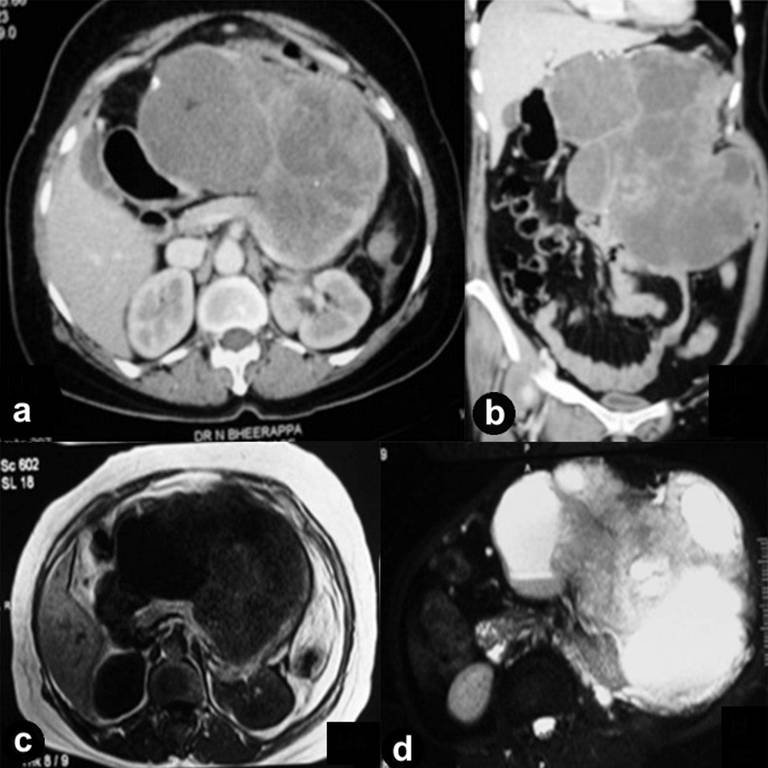

The accuracy of computerized tomogram (CT) imaging to predict a malignant vs. benign cystic lesion of the pancreas ranges between 76% and 82%. The accuracy of CT determination of the histopathological diagnosis of a pancreatic cystic lesion is less than 50% [54, 55]. Contrast enhanced abdominal computerized tomogram (CECT: 16/19, 84.2%), magnetic resonance imaging (MRI T1 and T2W: 5/19, 26.3%), transabdominal ultrasonography (US: 7/19, 36.8%), and endoscopic US (EUS: 3/19, 15.8%) [34, 37] with or without Doppler were used to localize, characterize, and delineate the tumors, for pre-operative fine needle aspiration (FNA) for diagnosis [34, 37, 43], and characterizing the associated pathology. Eight of 19 (42.1%) tumors occurred in the head of pancreas, 5 in tail (26.3%), 4 involved both body and tail (21.1%) and one occurred in the uncinate process (5.3%). Rarely (n=1, 5.3%) they did involve the entire pancreas [41]. The tumors ranged from few incidental masses to huge masses fulfilling the entire abdominal cavity. In most, the lesions were lobulated and showed heterogeneous enhancement in CECT and MRI with contrast (both solid and cystic/hemorrhagic). Padhi et al. [39] described the largest pEGIST (35x30x25 cm) which was hypointense in T1W MRI, hyperintense (cystic) with heterogeneous enhancement in T2W MRI (hemorrhagic and calcific foci) (Figure 1a-d). The lesions also showed variable vascularity with arterial phase enhancement of solid component [29, 34, 38, 39, 40]. The US features were that of predominantly hypoechoic (cystic/hemorrhagic/fluid like/? necrotic) masses with focal hyperechogenicities (? calcifications). However, in none there was any radiologic evidence of communication with or abnormality of major and/or minor pancreatic duct or bile duct, a feature supposed to be against the possibility of ductal adenocarcinoma [55]. Furthermore, in none tumor markers (CA 19-9 and carcinoembryonic antigen (CEA)) were found to be elevated, a finding that corroborated with the radiological findings.

Figure 1. Contrast-enhanced computerized tomogram of the abdomen: axial (a.) and coronal (b.) sections showing a large lobulated heterogeneously enhancing mixed echogenic lesion in the region of the body and the tail of the pancreas. On magnetic resonance imaging, the mass was hypointense on T1-weighted imaging (c.) and hyperintense on T2- weighted imaging (d.). |